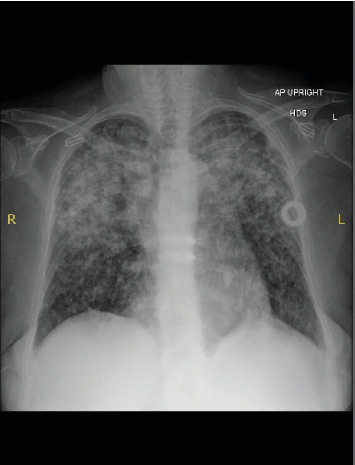

A 52-year-old female with a history of gastroesophageal reflux disease (GERD), hypertension (HTN), and supraventricular tachycardia (SVT) status postablation presented with progressive dyspnea and diffuse bilateral infiltrates on imaging. Symptoms began following exposure to a chicken farm, initially as a dry cough, evolving despite treatment with antibiotics, albuterol, and methylprednisolone. Emergency department CT imaging demonstrated bilateral linear, reticular, and nodular infiltrates. A negative infectious workup prompted bronchoscopy, confirming lung adenocarcinoma via immunohistochemical staining despite no significant smoking history, international travel, or other exposures. Brain MRI identified a solitary 7-mm enhancing lesion, guiding subsequent oncologic management. This case underscores the complexity of diagnosing atypical pulmonary symptoms and advocates for early bronchoscopic evaluation in suspected malignancies, particularly with pertinent family history.